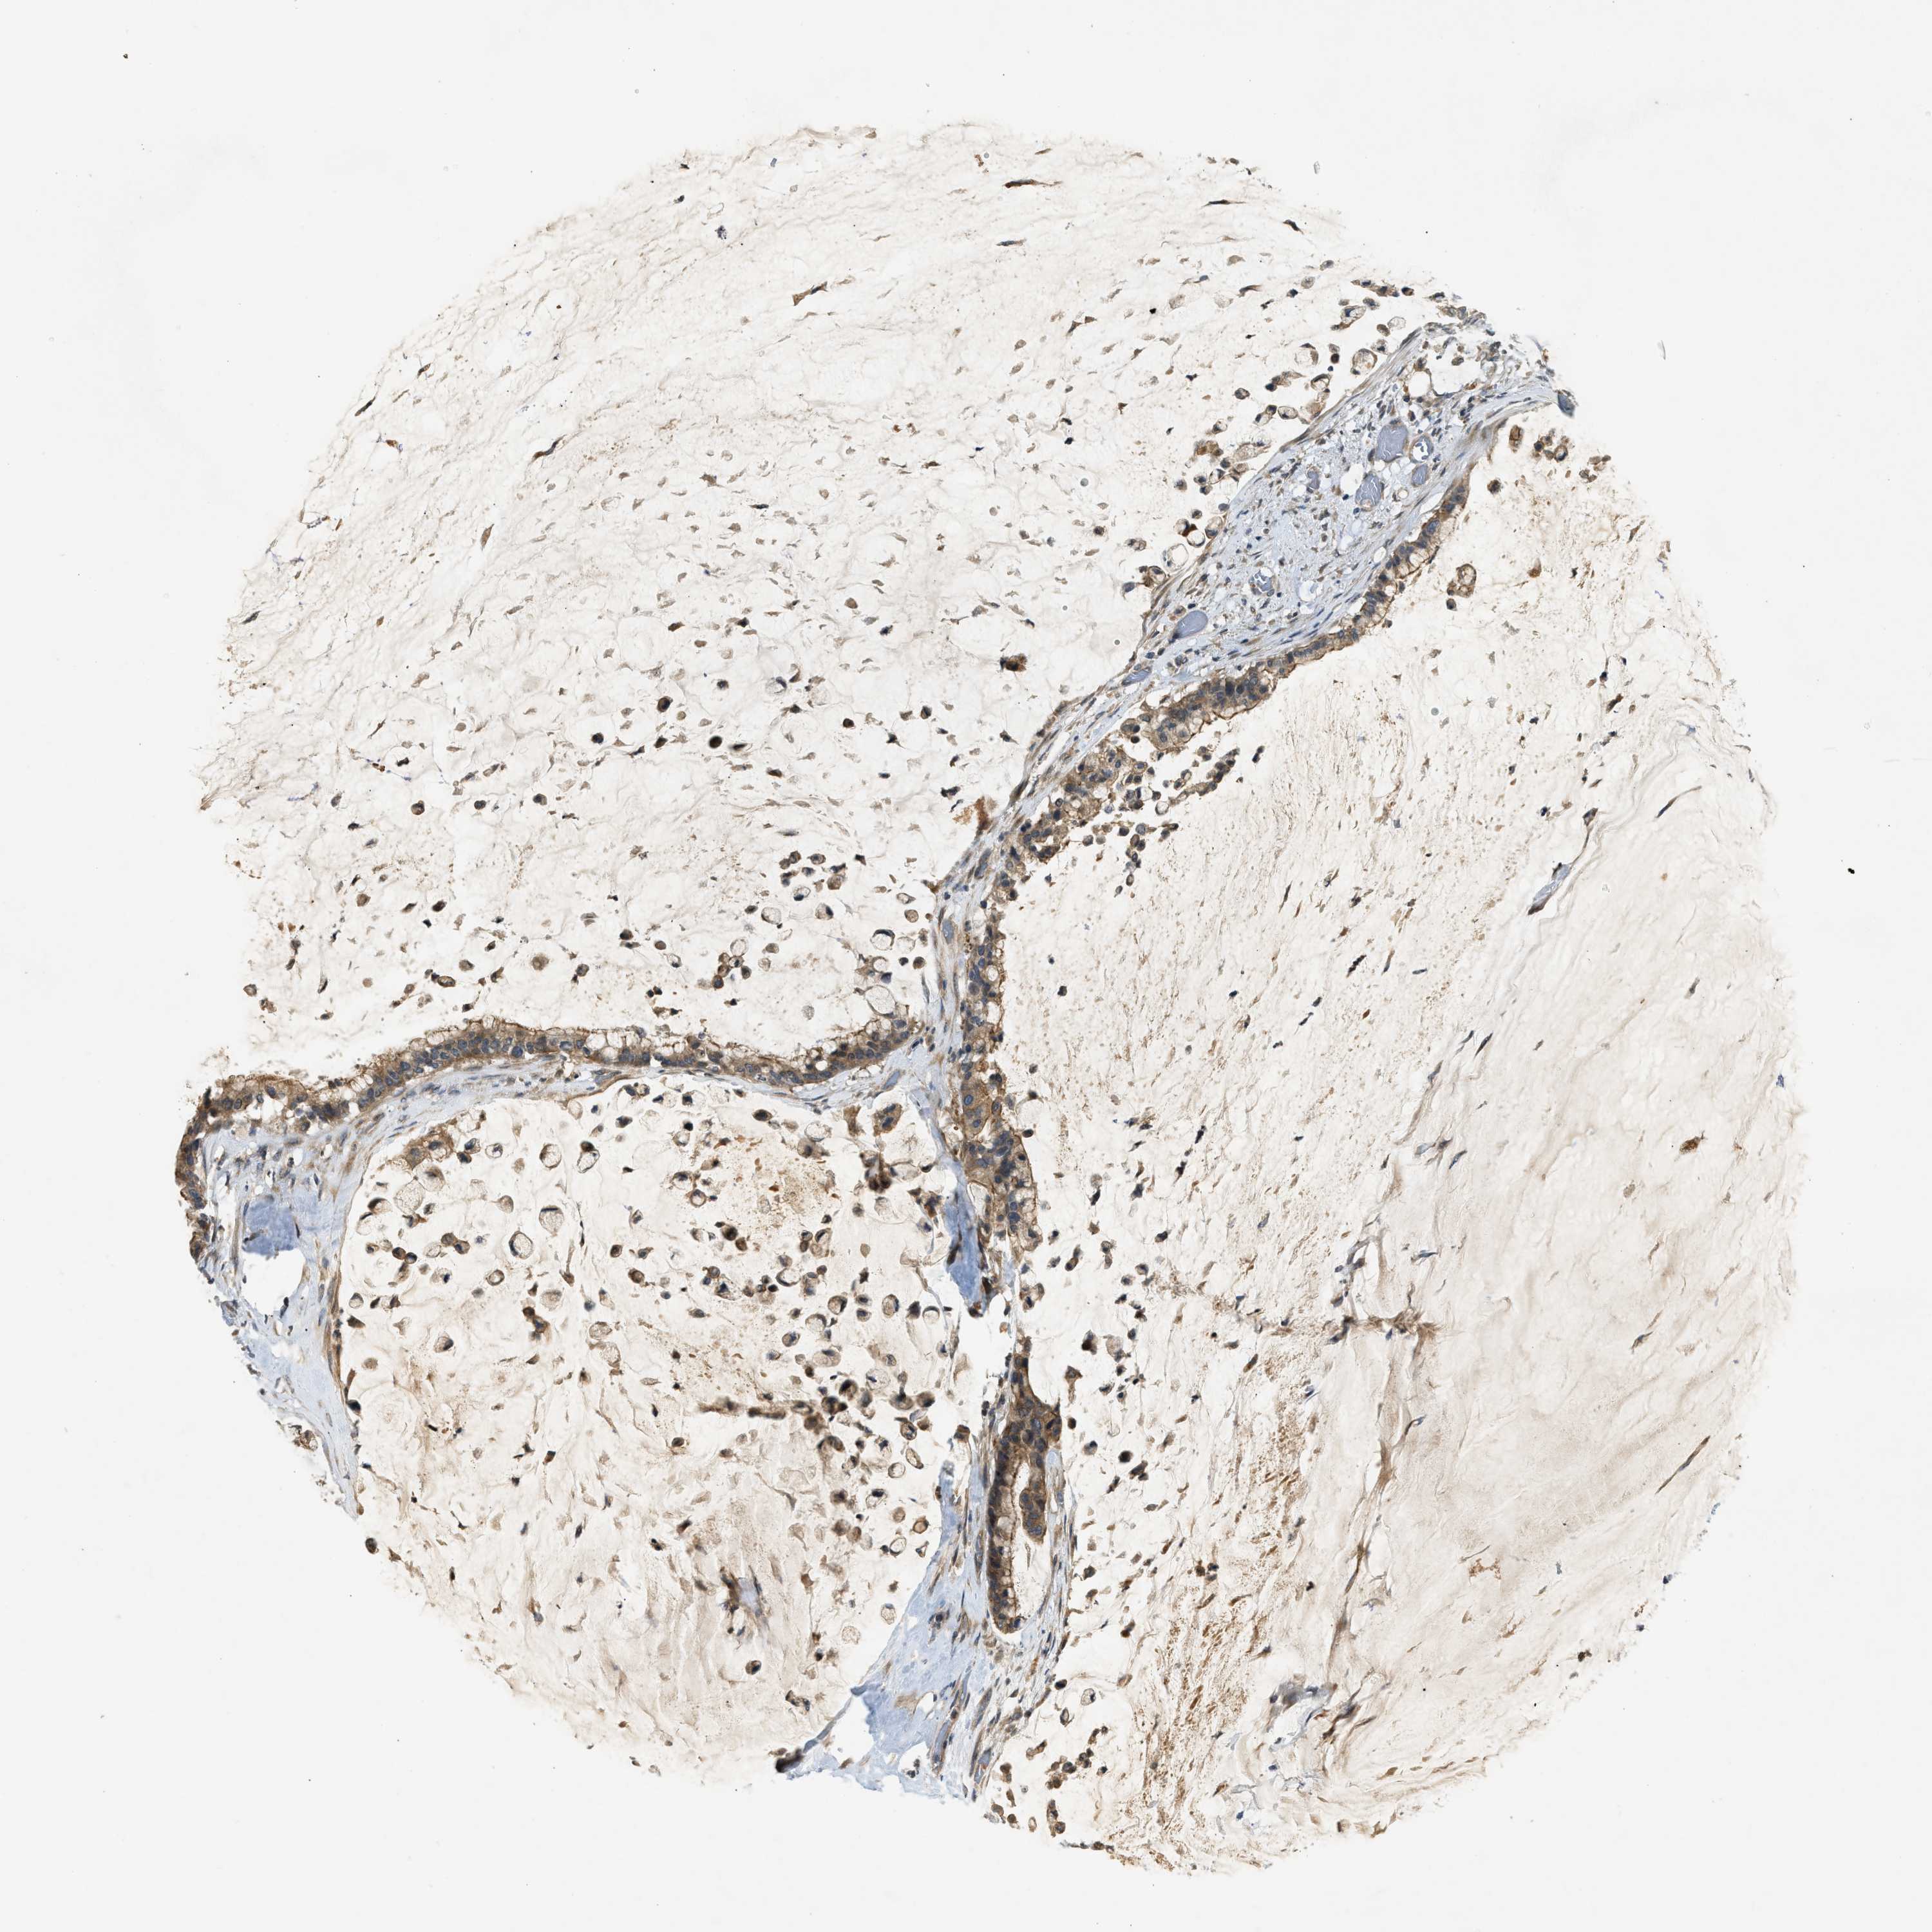

PANCREATIC CANCER - Protein expressioni

A mouse-over function shows sample information and annotation data. Click on an image to view it in a full screen mode. Samples can be filtered based on level of antibody staining by selecting one or several of the following categories: high, medium, low and not detected. The assay and annotation is described here.

Note that samples used for immunohistochemistry by the Human Protein Atlas do not correspond to samples in the TCGA dataset.

Antibody stainingi

Antibody staining in the annotated cell types in the current human tissue is reported as not detected, low, medium, or high, based on conventional immunohistochemistry profiling in selected tissues. This score is based on the combination of the staining intensity and fraction of stained cells.

Each image is clickable and will lead to virtual microscopy that enables deeper exploration of all samples and also displays staining intensity scores, fraction scores and subcellular localization as well as patient and tissue information for each sample.

Antibody HPA024291

Antibody CAB018652

Staining

High

Medium

Low

Not detected

Intensity

Strong

Moderate

Weak

Negative

Quantity

>75%

75%-25%

<25%

None

Location

Nuclear

Cytoplasmic/membranous

Cytoplasmic/membranous,nuclear

Adenocarcinoma, NOS